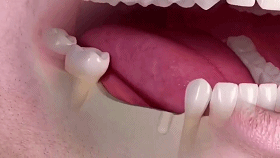

牙齒脫落是由齲齒、牙周病等口腔問(wèn)題導(dǎo)致的,不是單純的老化現(xiàn)象。牙齒健康至關(guān)重大,所謂“缺牙一顆,全口遭殃”,牙齒缺失一顆會(huì)引起鄰牙松動(dòng)、對(duì)牙伸長(zhǎng)、引發(fā)牙周病,終導(dǎo)致余牙逐漸脫落等一系列問(wèn)題,還會(huì)因咬合紊亂致使面容蒼老、咀嚼功能變差引發(fā)腸胃疾病,嚴(yán)重影響身體健康。

單顆牙種植

多顆牙種植

相比傳統(tǒng)固定義齒和活動(dòng)義齒,種植牙是醫(yī)學(xué)界公認(rèn)的理想修復(fù)方式,被譽(yù)為“人類的第三副牙”。相比活動(dòng)假牙不舒服、難清洗、容易引起口腔黏膜病變,種植牙更穩(wěn)固耐用,舒適美觀,咀嚼功能好,一次種植,即可重獲好口福!種植牙不僅是中老年人的專利,年輕人因意外、牙病等造成的單顆、多顆牙齒缺失,也能夠通過(guò)種植牙進(jìn)行修復(fù)調(diào)節(jié),重獲幸福笑容。